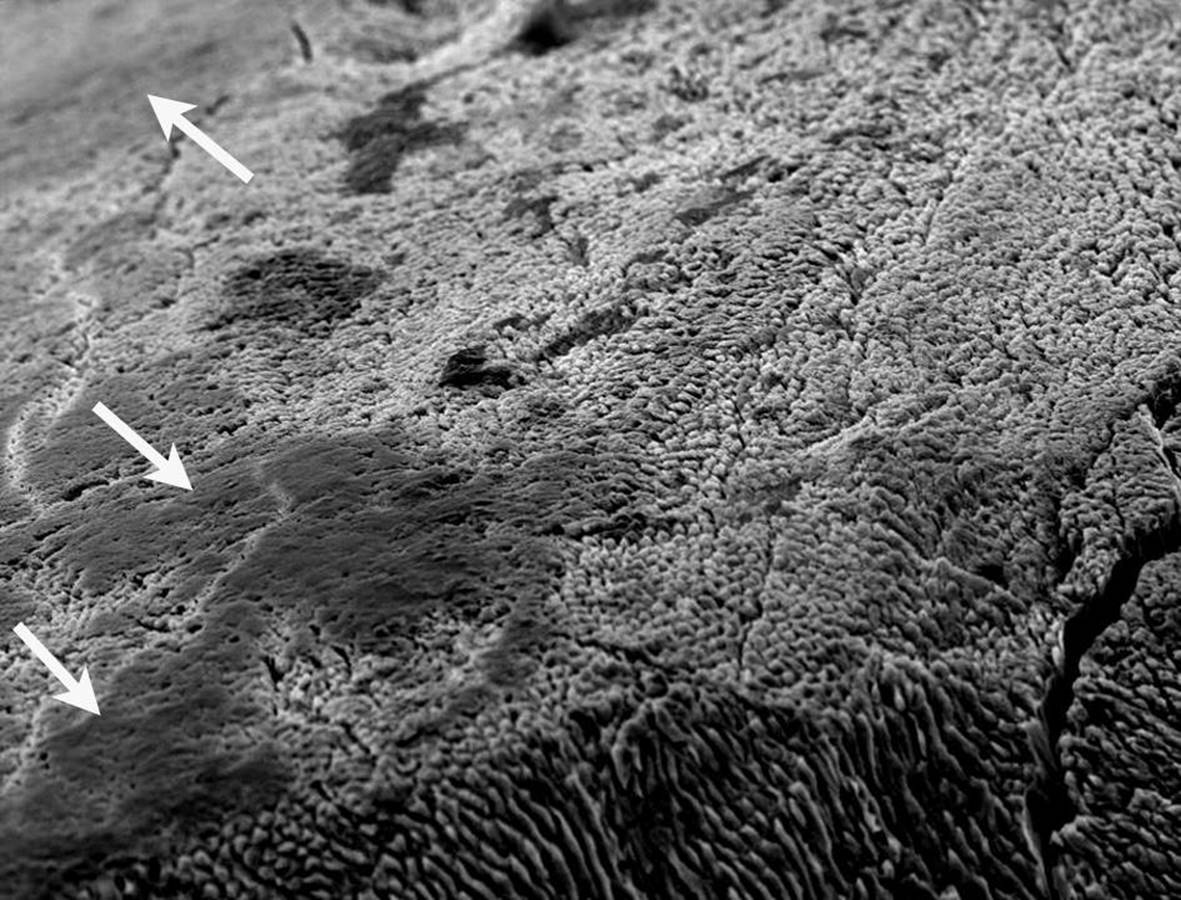

Particularly in pits and fissures, the probe should be used carefully in order to avoid iatrogenic damage (Figure 12.4). The probe is an important tactile aid and may be necessary to remove plaque. However, solely visual assessment of early (noncavitated) fissure caries lesions is not improved by probing [10]. In this context it is important to recognize that even if the probe “catches,” this does not necessarily mean that there is a soft lesion.

Figure 12.4 Sectioned premolar with an enamel caries lesion in the fissure before probing (left). Intense probing (right) destroys the surface zone of the lesion.